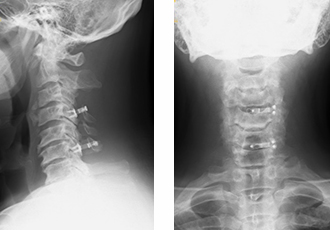

3. 頚椎手術(頚椎前方固定術、頚椎椎弓形成術、頚椎インストルメント手術)

頚椎手術は前方からあるいは後方から進入する方法に大きく2つに分かれます。頚椎前方固定術は頚椎を前から進入し、椎間板を郭清し、椎体を削って神経の圧迫を取り除き、金属製の内固定材(ケージ)と金属製のプレートで固定する手術です。必要に応じ骨盤や下腿から骨を採取します。また、骨を採取したあとの骨盤にはセラミックなどの人工物を補填する場合もあります。頚椎椎弓形成術は後方から脊柱管を広げ、脊髄の圧迫をとる手術です。手術の選択は患者さんの状態によって決定します。

① 頚椎前方固定術

頚椎を前から病巣を覚醒して骨盤の骨を移植して金属で固定しています。

② 頚椎後縦靭帯骨化症に対する頚椎前方固定術

頚椎を前から後縦靭帯を菲薄化して下肢の骨を移植して金属で固定しています。十分に除圧されています。

③ 椎弓形成術(後方手術)

後方から椎弓といわれる骨を削り脊柱管(神経の通り道)を拡大する方法です。

④ 頚椎後方インストルメント手術

後方から金属(インストルメント)を用いて固定します。多くは椎弓形成を追加します。

下の画像は透析脊髄症に対する再手術例です。インストルメントで頚椎を再建しています。